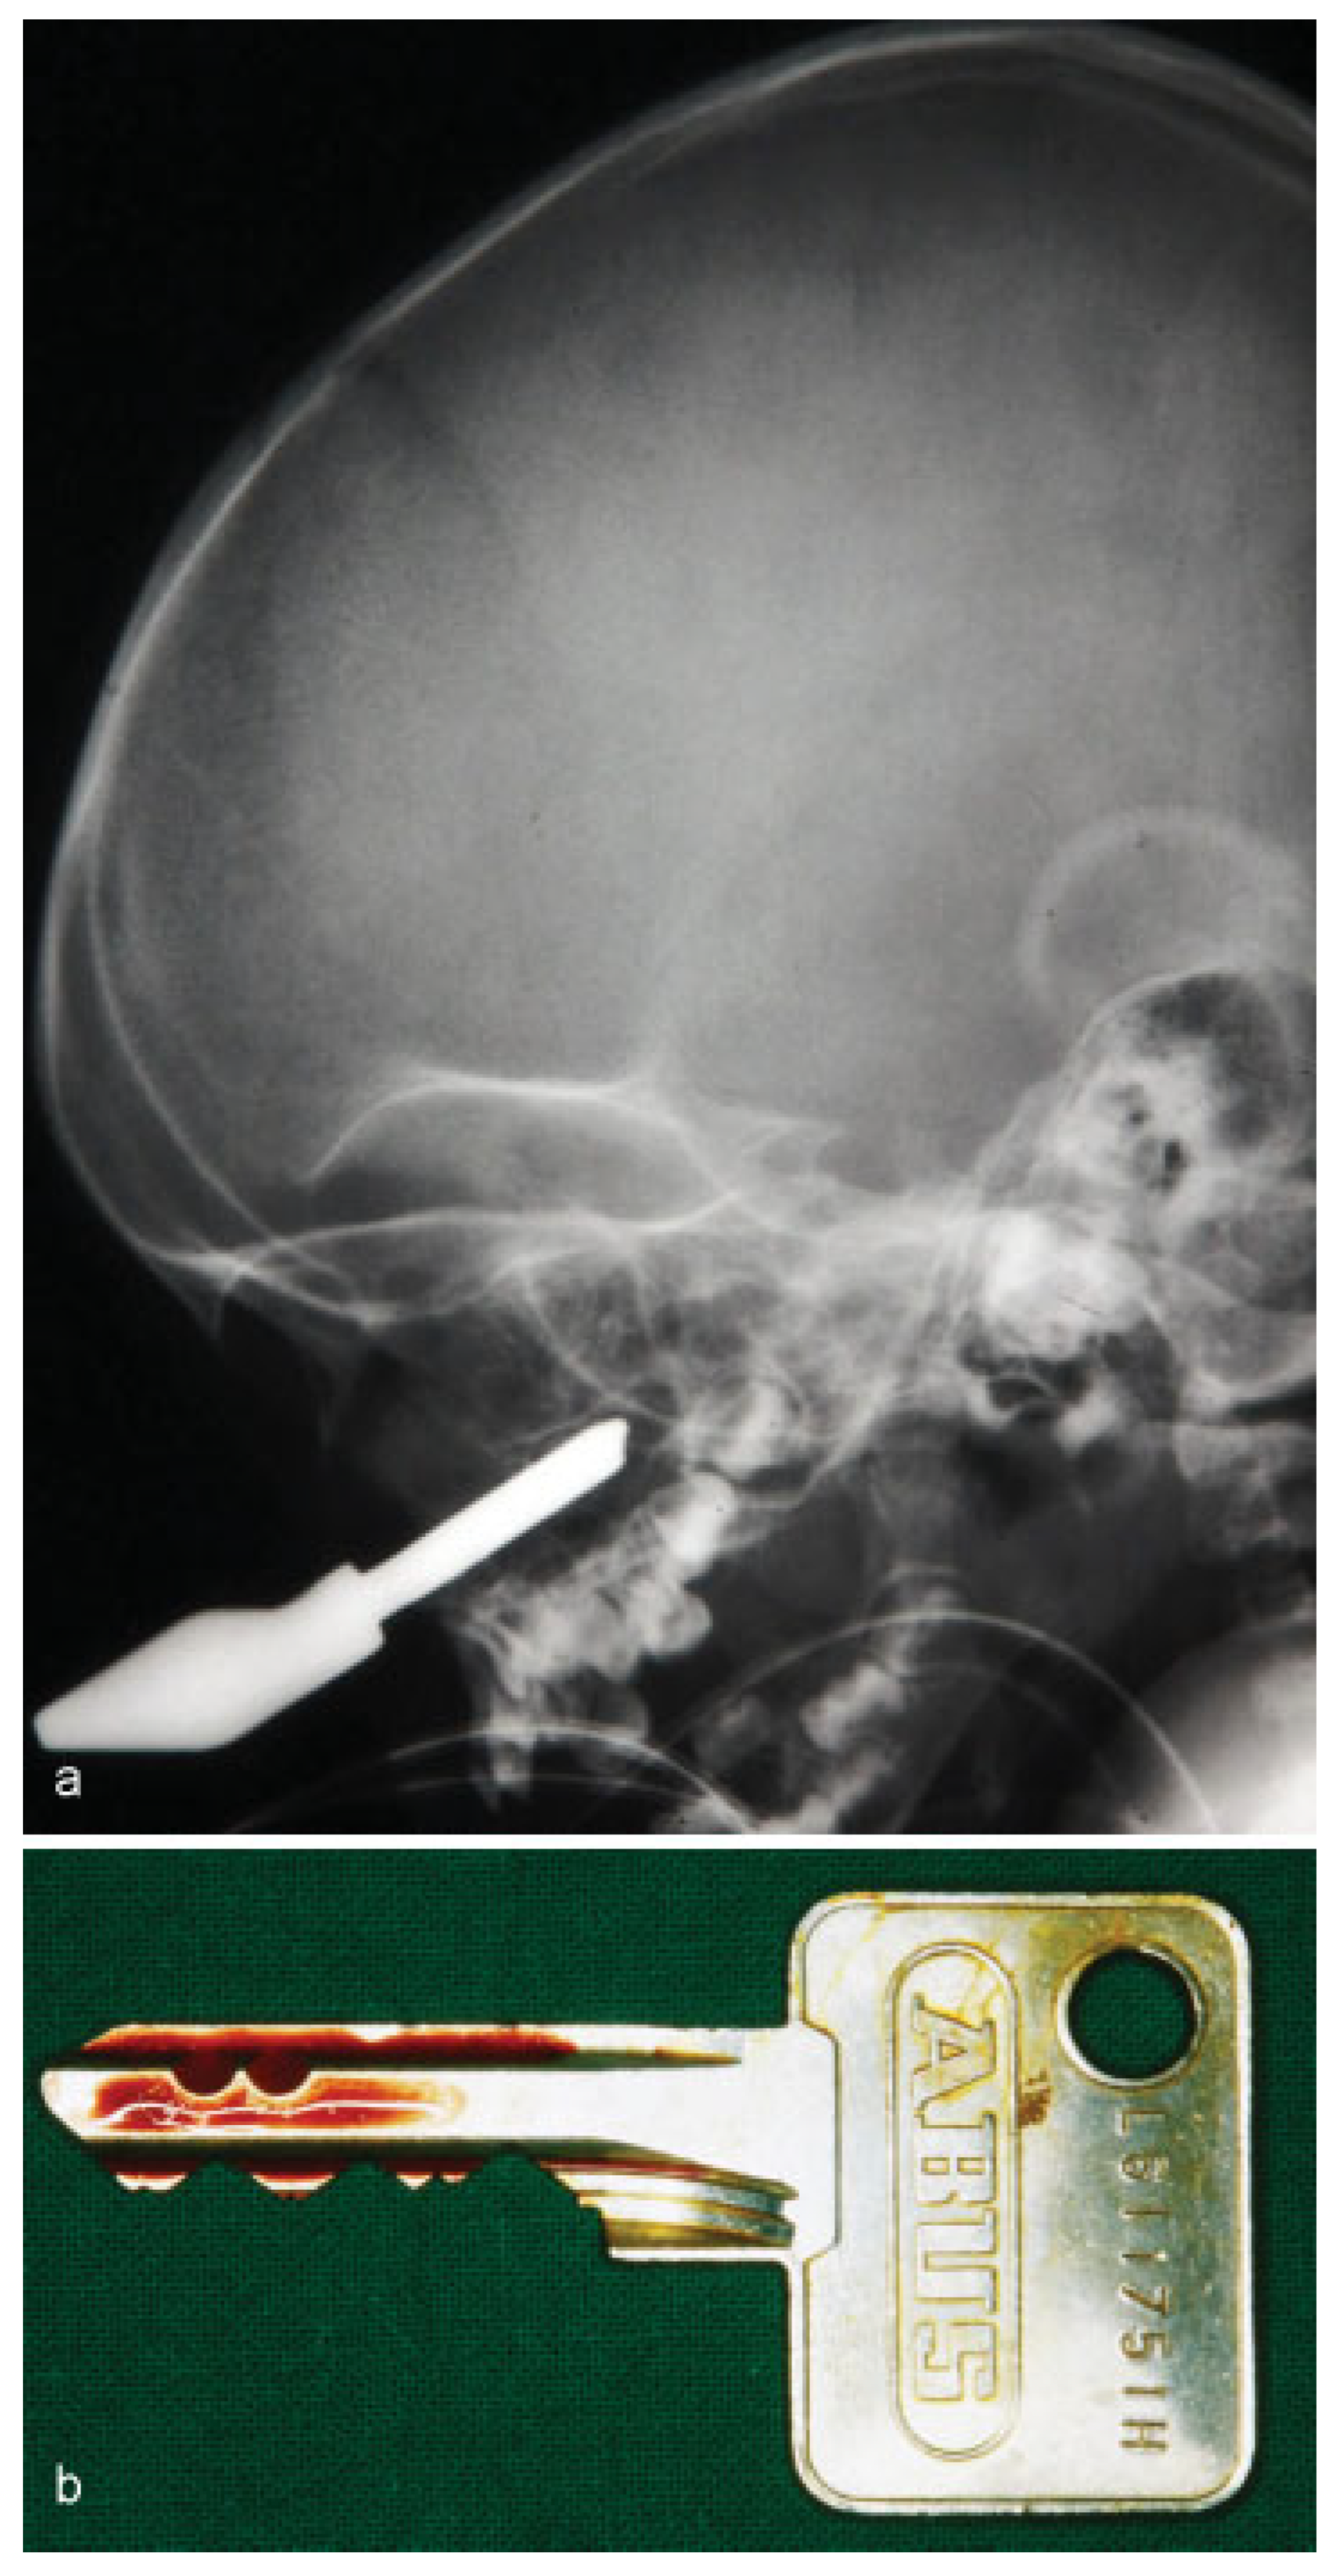

• Case 1: A 42-year-old patient was admitted to the emergency department after being hit by an Allen wrench at work. The impacted tool had penetrated the right orbit through the lower eyelid (Figure 1a). Multidetector computed tomography (MDCT) imaging confirmed a close proximity of the foreign object to the ocular bulb and the skull base, although neither of these structures appeared to be affected (Figure 1b). The patient was immediately taken into operating theater. Under general anesthesia, the penetration was extended by infraorbital incision to achieve a direct view of the orbit. In cooperation with ophthalmologists, the 8 × 1 cm tool was completely removed (Figure 1c). The postoperative outcome was uneventful with no visual impairment or diplopia.

Figure 1. (a) Lateral skull radiograph showing a radiopaque foreign object penetrating the orbital funnel close to the skull base. (b) Threedimensional reconstruction of a multidetector computed tomography scan demonstrating the position of the Allen wrench inside the orbital funnel. (c) Postoperative image of the removed Allen wrench.